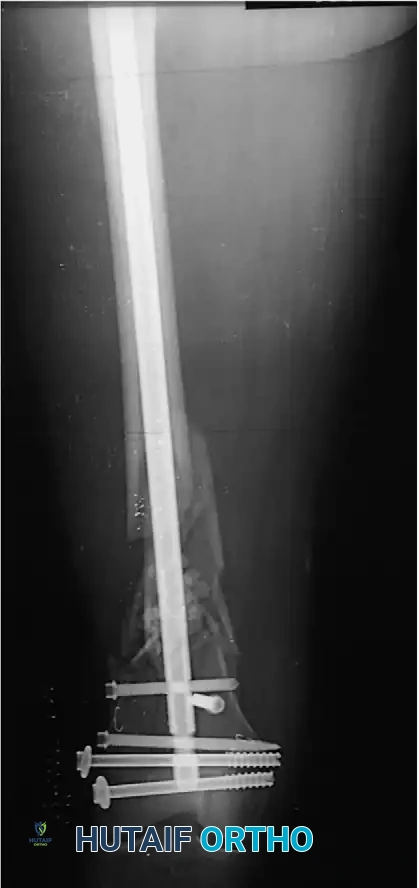

When an intramedullary nail, plate and screws, or external fixator is selected, the preoperative plan must rigorously account for the forces the fixation construct will sustain, the fatigue life of the implant, and the compliance of the patient. This biomechanical foresight dictates the postoperative rehabilitation program.

Locking Screws:

These are self-tapping screws with a threaded conical head that locks directly into a corresponding threaded hole in a locking plate. This creates a fixed-angle construct that does not rely on friction between the plate and bone, making it ideal for osteoporotic bone or complex comminuted fractures.